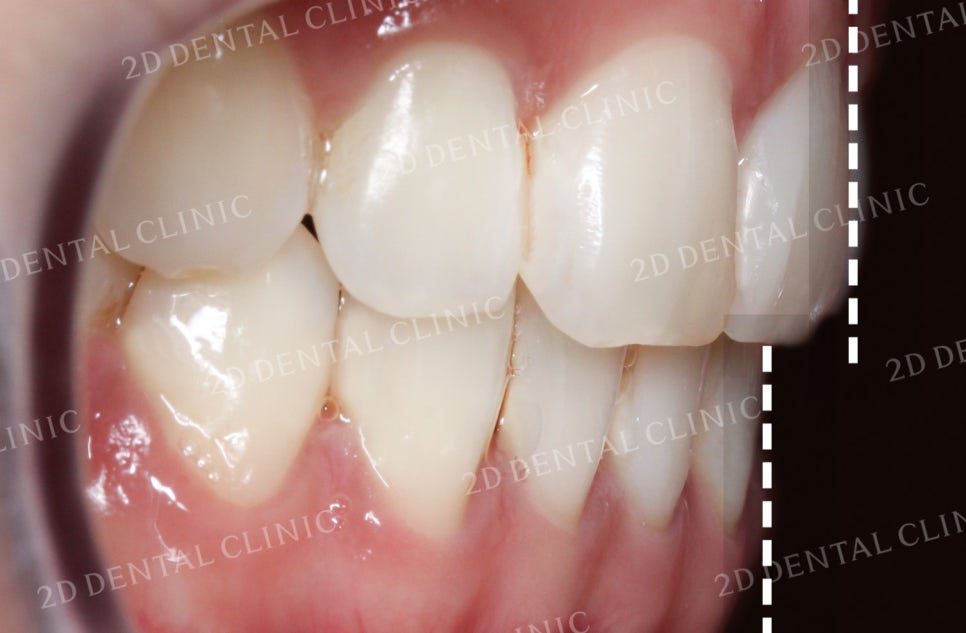

좌우의 안모 사진입니다.

표시된 부분에서 완전히 맞물리지 못한

치아 사이의 틈이 발견되고 있네요.

이러한 교합면 사이의 빈 공간은

음식물 섭취 시 불편을 유발하는 원인 중 하나입니다.

좌측의 안모 사진입니다.

치열의 총생으로 인해

송곳니 부근에 생겼던 틈들이

잘 덮혀진 모습입니다.

우측 역시 비어있던 공간이

상악의 교정치료 후